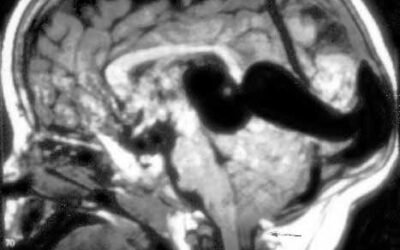

Prenatal diagnosis of cerebral vascular malformations: case series

To describe the ultrasound findings and perinatal out- comes of cases with a prenatal diagnosis of cerebral vascular malformations (CVM)